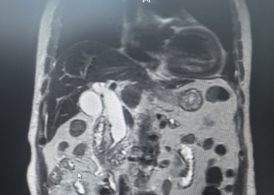

在吴文广教授的指导下,团队成功为一名56岁的胰腺癌患者实施了ERCP手术。检查提示“胰腺头颈部恶性肿瘤伴肝内外胆管及胰腺体尾部主胰管扩张”,针对患者病情,吴文广教授带领团队在术前展开充分讨论,制订了缜密的治疗方案,在与患者及家属充分沟通后最终决定通过内镜下放置胆管支架、胰管支架,为患者解除梗阻。术中,在吴文广教授的指导下,杨晨组长带领团队经预切开、插管、造影、支架置入等一系列操作,团队成功解除了胆道梗阻,最终成功引流出黑色胆汁,手术取得成功。